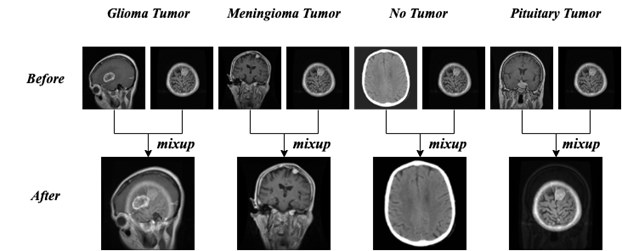

2.2.2 Mixup

The second algorithm is Mixup, which is a data enhancement method based on the principle of neighborhood risk minimization, using linear interpolation to obtain new sample data. Assuming that it is a batch sample, which is the label corresponding to that batch sample; it is another batch sample, which is the label corresponding to that batch sample, and it is the mixing coefficients computed from the Beta distribution of the parameters α, β. The principle formula is shown in Equation 1 as follows.

In the mixup data enhancement process, we randomly select samples to operate with it, and the specific effect is shown in Fig 4.